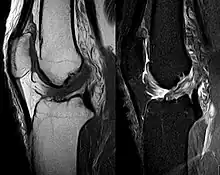

Procédés d'imagerie

Le diagnostic peut être confirmé par imagerie (IRM). Mais il faut noter que l'interprétation de l'IRM seule pour le diagnostic de rupture de LC conduit à 20 % de faux diagnostics. Cela dépend des images de coupe et de la position appropriée du genou pendant l'IRM. Le radiologue doit connaître avec précision les circonstances qui ont conduit à la blessure, et avoir aussi une bonne expérience de l'étude d'une articulation blessée, pour éviter les faux diagnostics. Pour comparer avec l'IRM, le taux d'erreur du test de Lachman, bien plus simple à accomplir, n'est que de 10 %[106],[107],[108],[109]. L'IRM est donc généralement moins sensible et moins spécifique que l'examen clinique par un orthopédiste qualifié[110]. Le résultat de l'IRM n'a que relativement rarement une influence sur la formulation finale du diagnostic[111] et ne devrait pas servir de remplacement pour une anamnèse soigneuse et la palpation[112]. Plusieurs études arrivent à la conclusion que l'IRM n'a de sens que pour des blessures complexes difficiles à expliquer, et là, pour éviter de poser un diagnostic négatif[113],[114],[115].